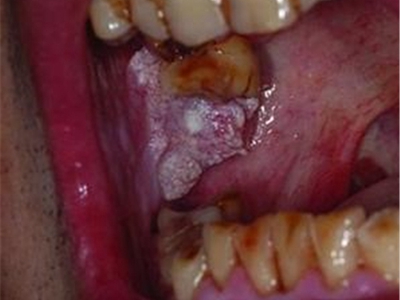

口腔

肿块 · 白斑

颊癌颊黏膜长肿块糜烂发白图

颊癌发生于右侧颊黏膜时,口腔检查见患者磨牙处的颊黏膜有一肿块,肿块表面有溃疡糜烂,形状不规则,如花生豆大小,表面有灰白色假膜,伴有剧烈疼痛。